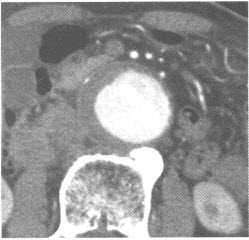

男性,70岁。行腹部CT增强扫描,发现腹主动脉异常如下图。

应诊断为()

A、主动脉血栓形成

B、主动脉硬化

C、主动脉瘤并附壁血栓

D、主动脉夹层动脉瘤

E、主动脉破裂

C